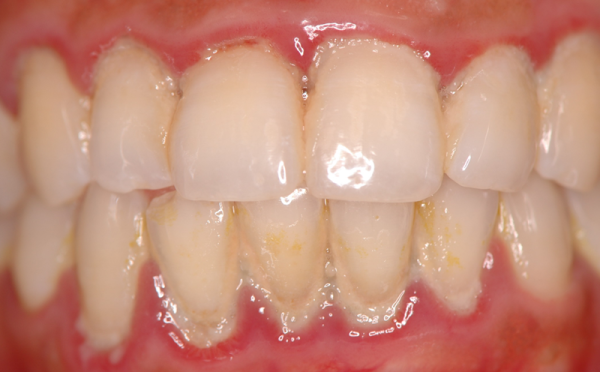

치료 전과 치료 후는 이렇게 달라집니다.